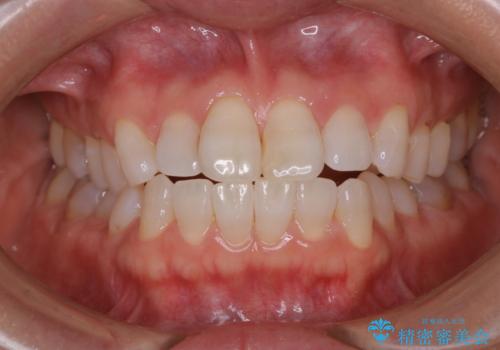

歯科衛生士によるPMTCでお口のケア

- 歯医者に来院することが久しぶりで、まずはクリーニングを希望とのことでした。コースや内容は、一番状態に合ったものでとのことだったため、PMTC60分コースを行いました。

PMTCとは「Professional Mechanical Tooth Cleaning」の略で、専用の機器を使った歯のクリーニングです。

定期的に歯科医院に来院し、PMTCを行うことが大切です。

- 保険適用外となります